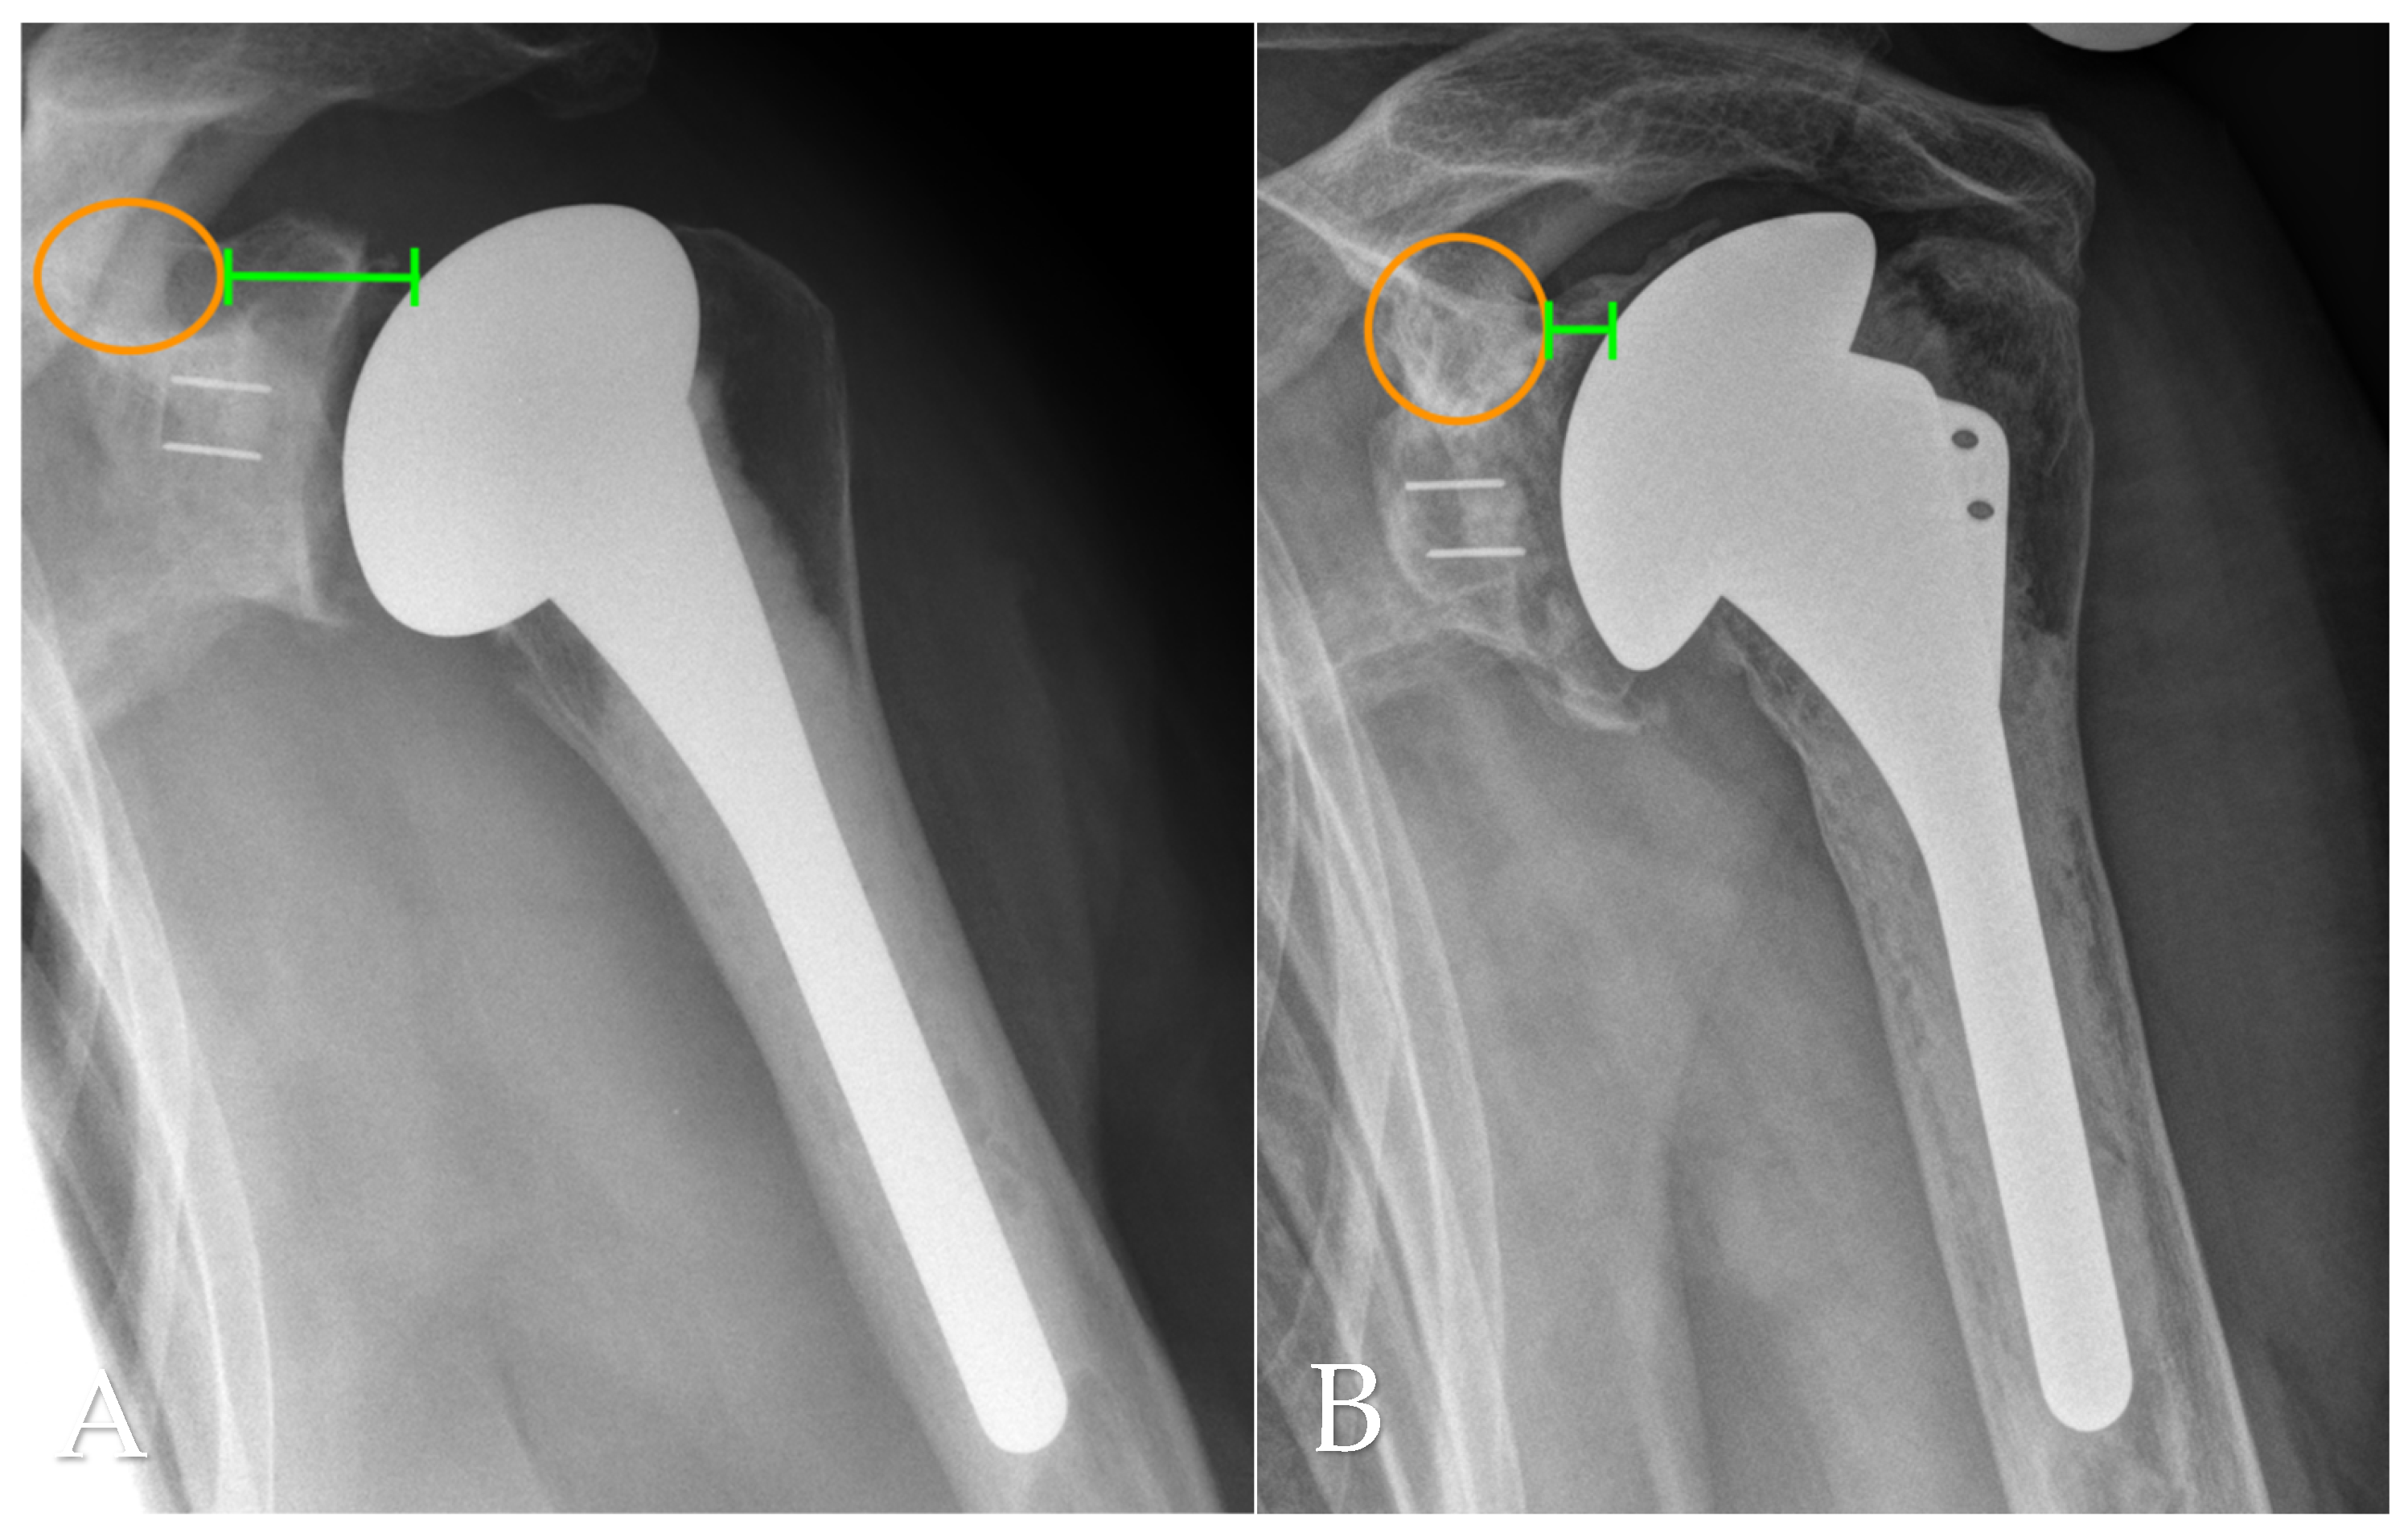

2.4. Radiographic Assessment